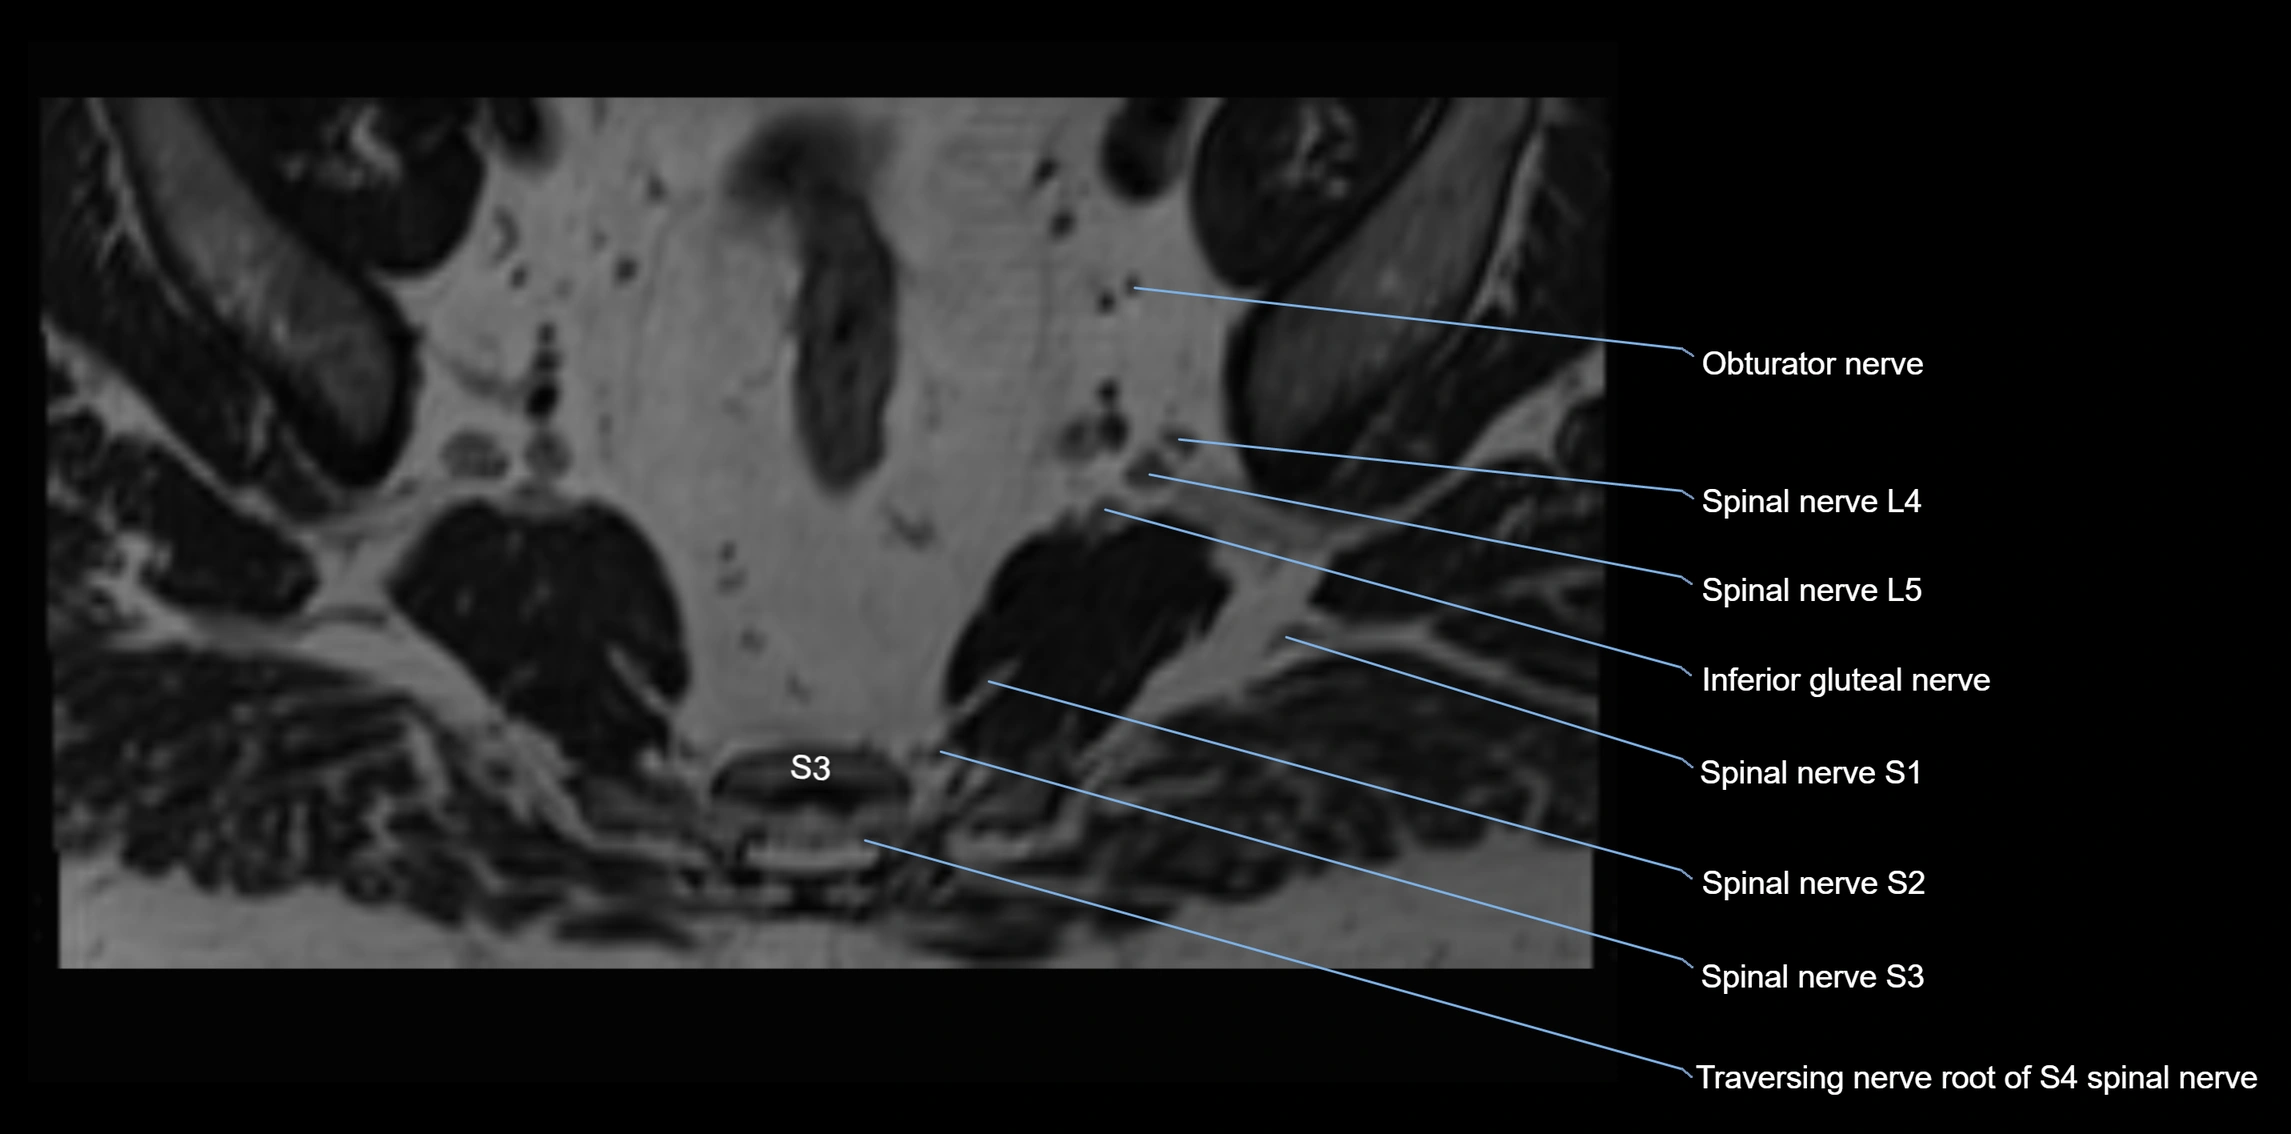

MRI Appearance

T1-weighted images:

• Nerve appears as a very thin low-to-intermediate signal intensity structure

• Surrounded by bright fat, aiding visualization

T2-weighted images:

• Nerve shows intermediate to mildly hyperintense signal compared to muscle

• Pathological involvement appears brighter

STIR (Short Tau Inversion Recovery):

• Normal nerve appears dark

• Inflamed or entrapped nerve appears bright hyperintense

T1 Fat-Sat Post-Contrast:

• Normal nerve enhances minimally

• Pathologic nerve (neuritis, entrapment, tumor infiltration) shows focal or diffuse enhancement

3D T2 SPACE / CISS:

• Nerve appears intermediate to mildly hyperintense compared to muscle

• Surrounded by bright fat or CSF, improving visualization

• Best sequence for mapping small pelvic nerves such as the anococcygeal